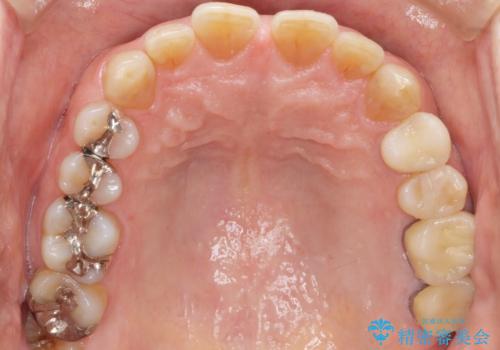

精査したところ、奥歯(左上67)の根尖部に位置した歯茎に瘻孔(膿の出口)ができており、CTを撮影し確認すると奥歯2本(左上67)の根尖病変は大きくつながっていました。

銀座しらゆり歯科の林院長による精密根管治療を受けて頂いたのち、メタルボンドクラウンによる補綴を行いました。